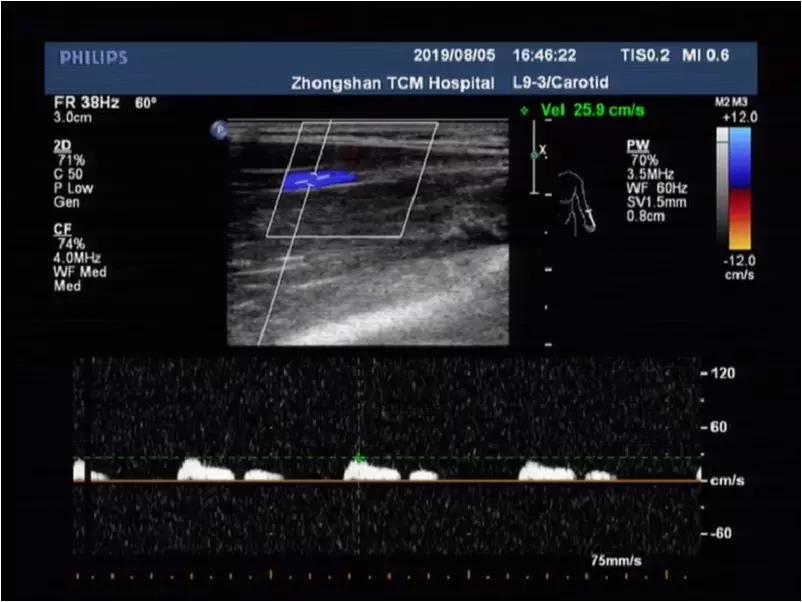

(左图)自然体位:锁骨下静脉受呼吸影响的正常期相频谱;(右图)上举体位:锁骨下静脉不受呼吸影响(进一步提示本病!)